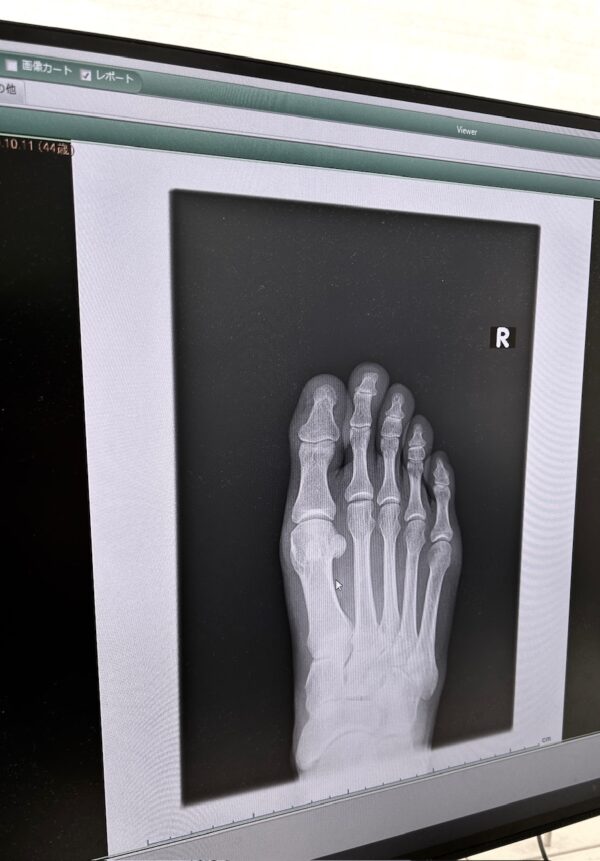

骨osatokyo

(種子骨にびびる)

大した異常が無かった事は

二十年前の自動二輪車事故

で潰れた骨も綺麗

(中指薬指小指の付け根)